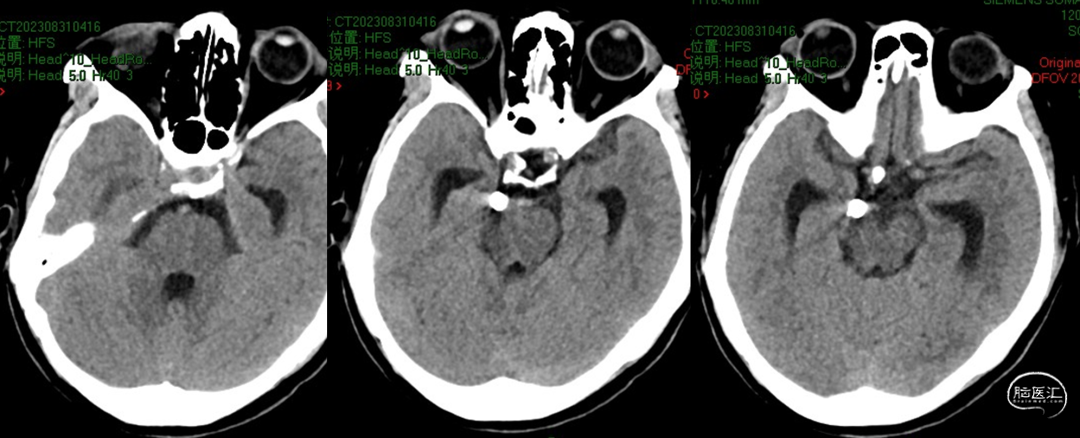

2023-08-29

我院CT

2023-08-30

2023-08-31

术后CT